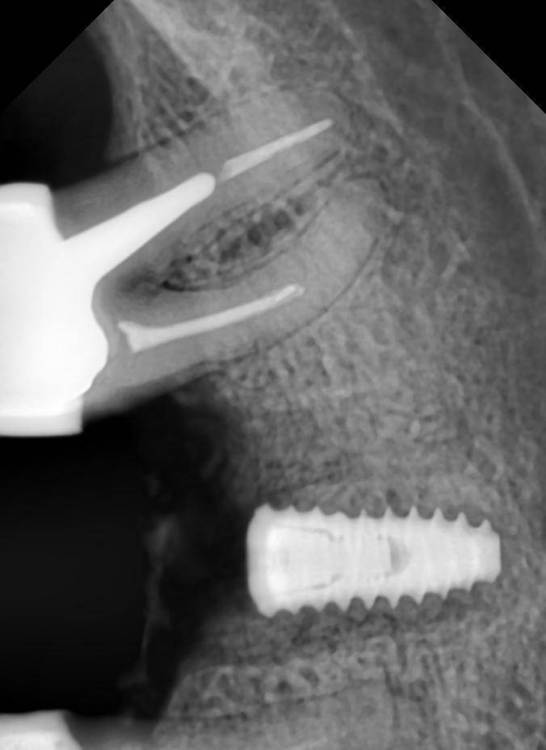

Jonik Опубликовано 6 февраля, 2022 Автор Поделиться Опубликовано 6 февраля, 2022 48 минут назад, Irouil сказал: @Jonik 5-го, который на снимке «слева», без вкладки По предоставленной рентгенограмме создаётся ощущение, что у верхушки корня присутствует воспаление. Если зуб не подвергался лечению в течении последних 12 месяцев - на него стоит обратить внимание Каналы этого зуба были запломбированы лет 20 назад, есть подозрение что резорцин ("остекленели" давно, может непроходимые уже), сам зуб потемнел, наполовину из пломбы состоит. Планирую в ближайшее время закрыть его коронкой. Как думаете, стоит ли лезть в каналы и пытаться перелечить или закрывать как есть? Ссылка на комментарий

Pavel-Pskov Опубликовано 7 февраля, 2022 Поделиться Опубликовано 7 февраля, 2022 Все выглядит нормально Кроме соседнего зуба Кроме обоих. Ссылка на комментарий

annda Опубликовано 7 февраля, 2022 Поделиться Опубликовано 7 февраля, 2022 Если там 20-летние резорцинки, да еще и под вкладкой, оставьте их в покое, пусть протезируют как есть. Сколько простоят. Там даже просветов каналов не видно , чтобы говорить о перспективах перелечивания. 1 Ссылка на комментарий